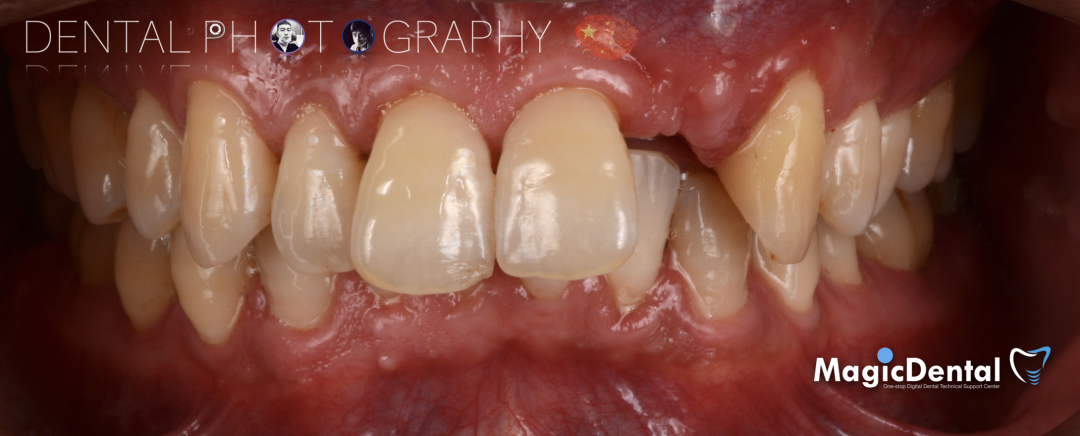

患者术前口内照片

既往史:既往体健,无其他系统病史,否认重大疾病史,有口腔拔牙史。口腔检查:口腔卫生良好,牙周状况良好,22缺失,缺失间隙约7mm,CT显示缺失牙位置唇颚侧骨壁薄,无对颌伸长,邻牙无移位,上下前牙呈深覆 ,38、48近中阻生。

22缺失,且牙槽骨唇颚侧宽度较窄,38,48近中阻生。

治疗计划:水平骨增量,拔除四区近中阻生智齿,下颌升支外斜线处取块状骨,移植骨块至受区(22唇侧),种植修复22缺失牙。

术后三个月口内正面像

术前术后对比